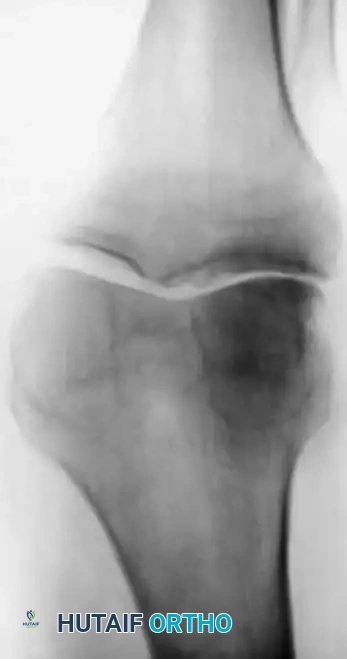

When osteoarthritis is unicompartmental and associated with mechanical malalignment (varus or valgus), corrective osteotomy is a powerful joint-preserving procedure. By realigning the mechanical axis, load is transferred from the diseased compartment to the relatively healthy compartment.

High Tibial Osteotomy (HTO)

HTO is primarily indicated for medial compartment osteoarthritis associated with varus deformity. The goal is to shift the mechanical weight-bearing axis slightly lateral to the midline of the knee joint (the Fujisawa point, typically 62% of the tibial width from the medial edge).

Surgical Atlas: Osteotomy and Realignment Biomechanics

The following radiographic and illustrative figures detail the preoperative planning, biomechanical axes, and intraoperative fixation strategies critical for successful osteotomies around the knee.

Preoperative templating is mandatory. The mechanical axis must be drawn from the center of the femoral head to the center of the ankle mortise. The degree of correction is calculated to ensure the new weight-bearing line passes through the targeted compartment.